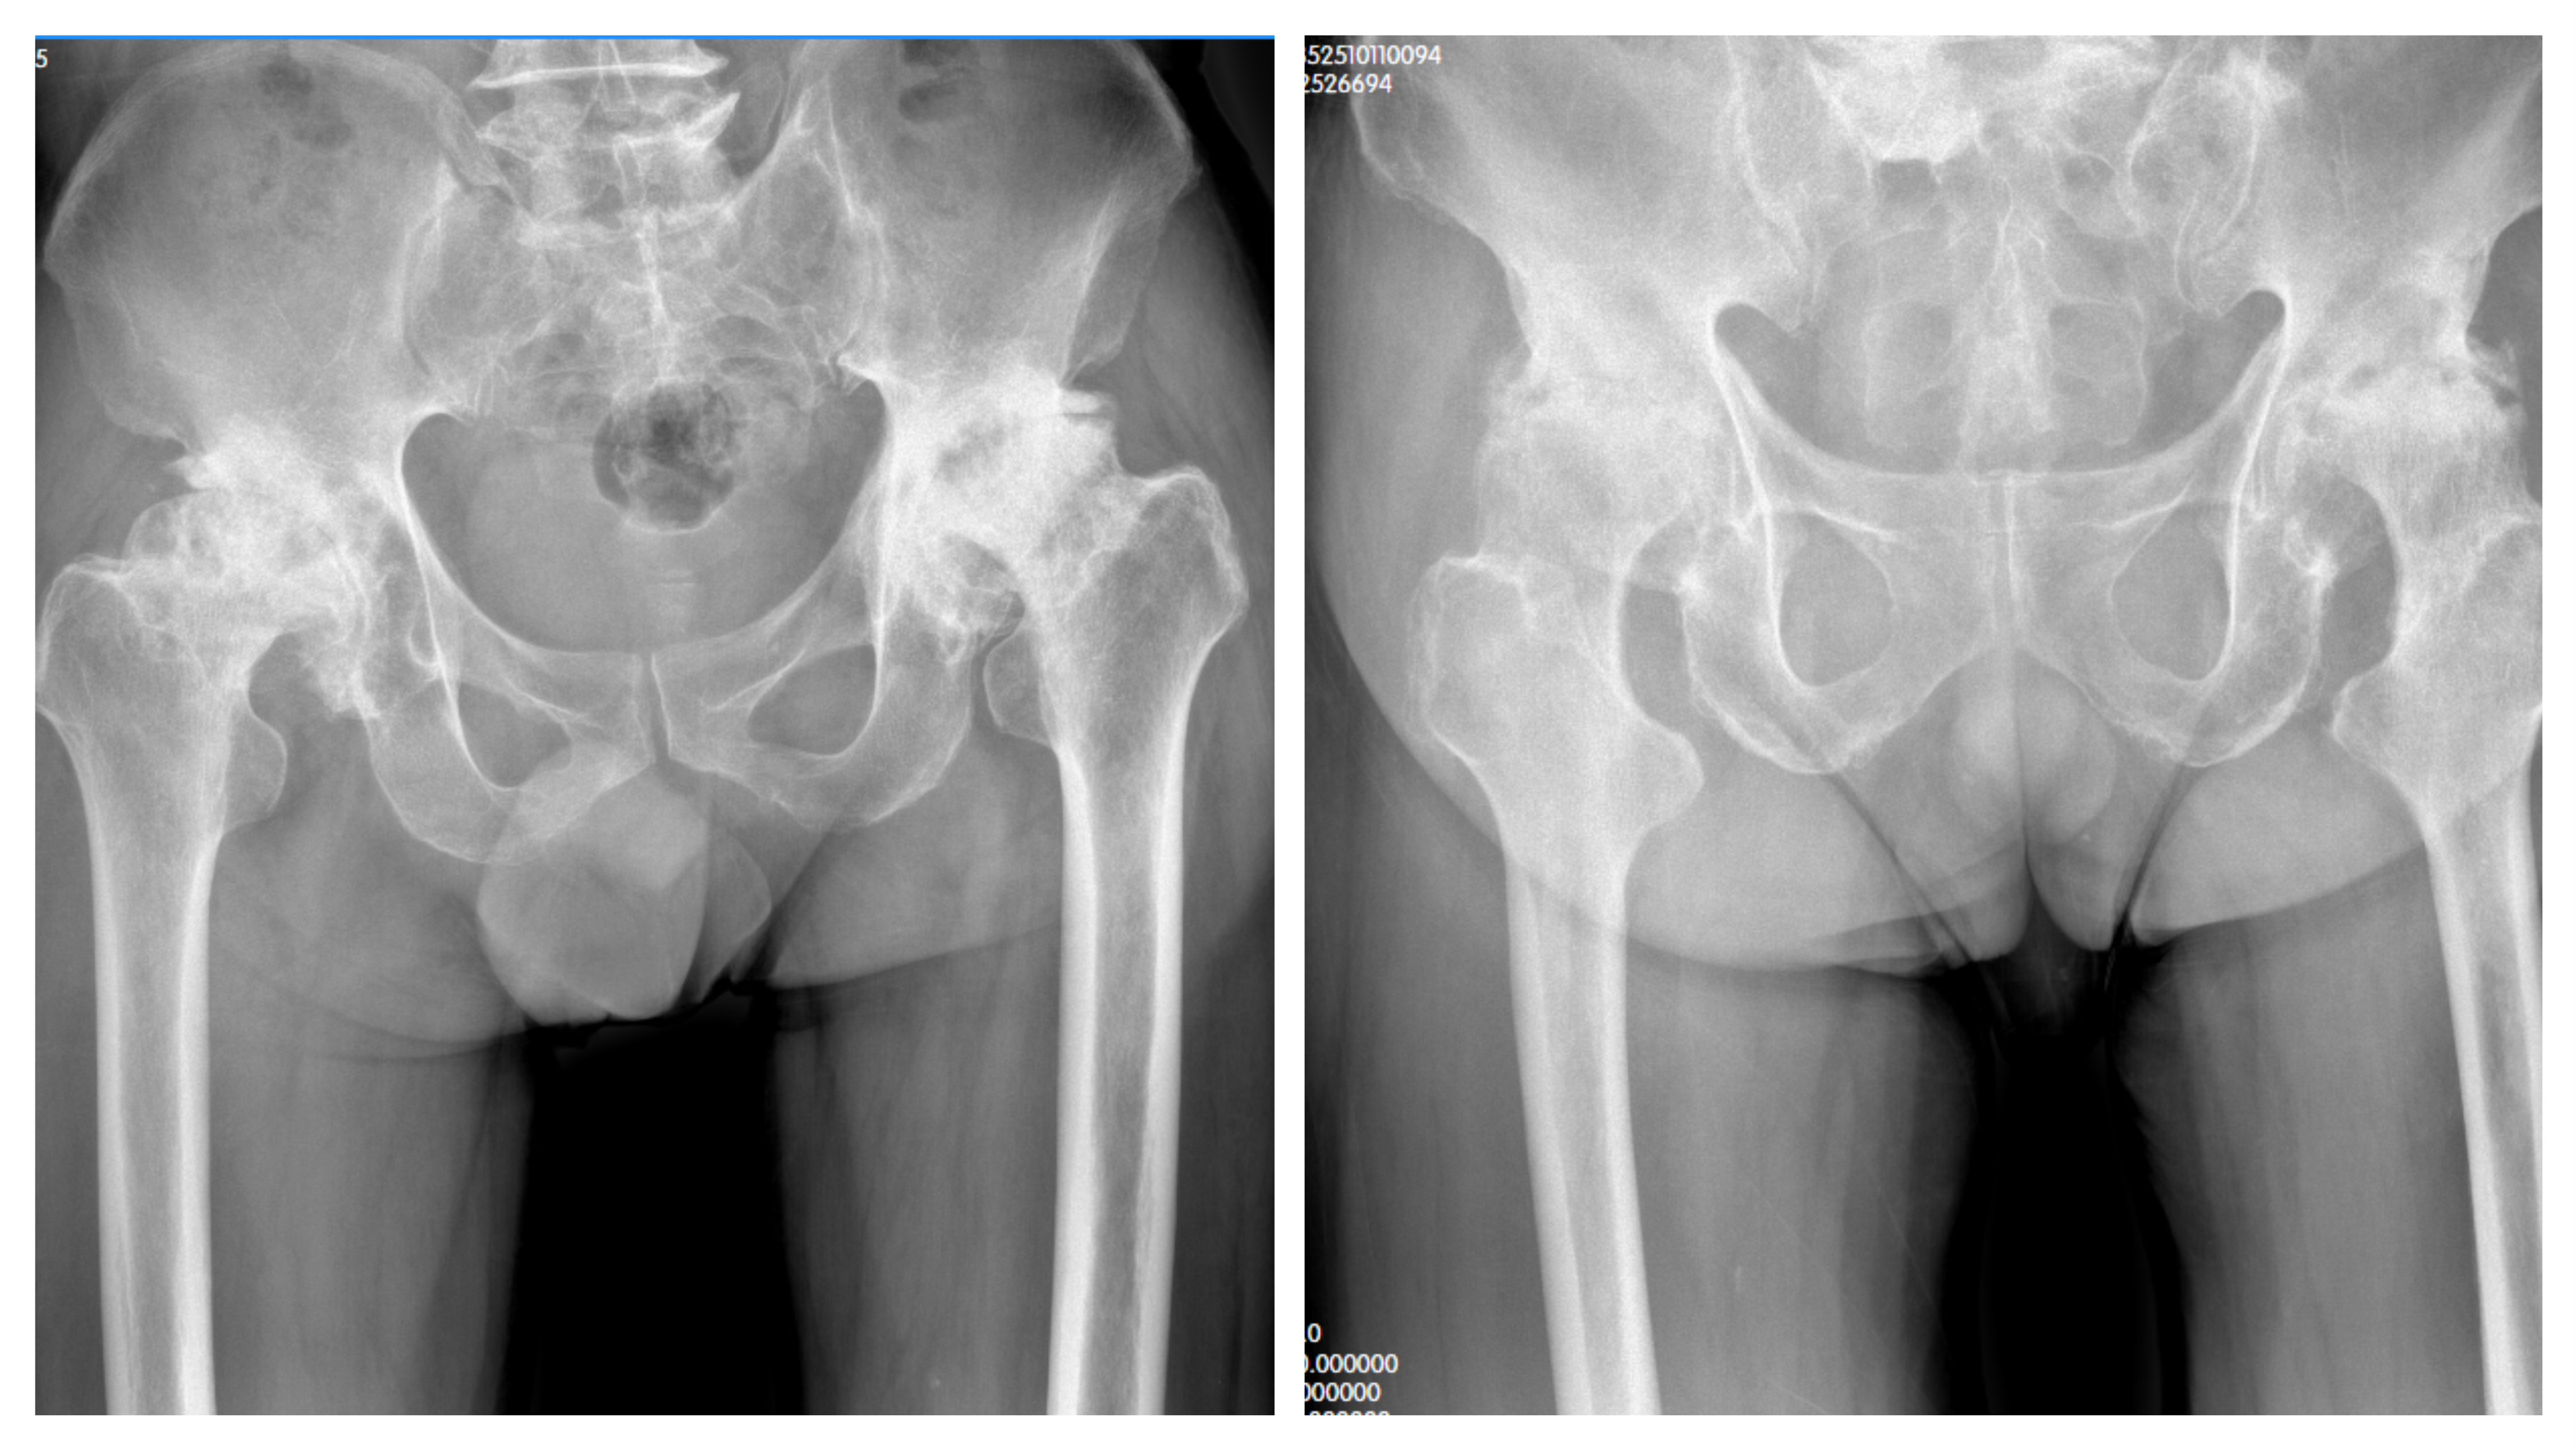

△两叔侄检查结果提示:“股骨头缺血性坏死”

在筹备就医时,杨叔叔想起自己79岁的亲叔叔杨爷爷,同样被髋关节疼痛折磨了整整十年,病情更为严峻。除了双髋功能活动障碍逐年加重、伴随跛行外,杨爷爷还出现了下肢短缩的情况,生活自理都成了难题。为了获得专业治疗,叔侄二人商量后,决定一同前往重庆长城骨科医院关节外科就诊。经门诊详细检查,两人均被确诊为“股骨头缺血性坏死”,并被收治住院。